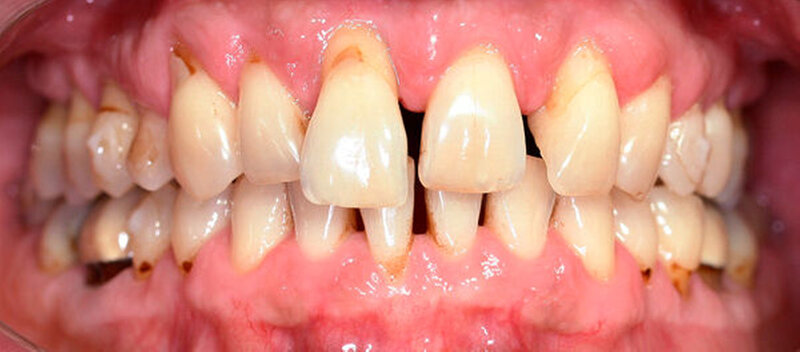

Anamnestisch lagen keine Besonderheiten vor. Es ist jedoch zu vermerken, dass ein regelmäßiger Alkohol-, Koffein- und Nikotinkonsum zugrunde lag. Intraoral zeigte sich ein bereits konservierend versorgtes permanentes Gebiss mit aktivem und inaktivem kariösen Geschehen. Große Anteile der Zahnhälse lagen nach Zahnfleischrückgang in Kombination mit Knocheneinbrüchen frei. Zahn 27 wurde bereits extrahiert.

Eine Beurteilung der parodontalen Situation an Zahn 11 offenbarte mesial und distal Sondierungstiefen von jeweils 6 mm.

Kieferorthopädisch imponierte beidseits eine neutrale Verzahnung bei einem tiefen Biss von 5 mm – bedingt durch die Verlängerung beider Frontzahngruppen. Besonders Zahn 11 zeigte eine erhebliche Verlängerung und Protrusion mit einer sagittalen Frontzahnstufe von 5 mm. Sowohl die Frontzähne im Ober- als auch im Unterkiefer wiesen eine lückige Beziehung zueinander auf (Abbildung 1).